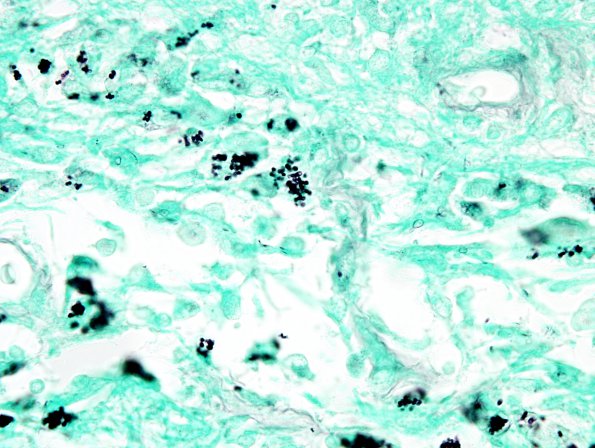

Higher magnification of the fungi seen in image #5C5 are most consistent with Candida glabrata (GMS)